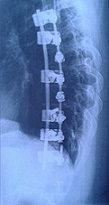

Nachdem bei mir mit 8 eher zufällig eine Skoliose entdeckt wurde (war im Winter ausgerutscht und auf den Rücken gefallen - Brustwirbel angebrochen, 18° in der Hauptkrümmung), habe ich mit 9 mein erstes Korsett bekommen, da waren es schon 28°. Nach einem falschen Korsett, einem Arzt- und Sanitäthauswechsel, einer Kur in Bad Elster mit 13 und einer täglichen Korsett-Tragezeit von 15-17 Stunden sowie Physiotherapie kam ich dann mit 14 (2002) trotzdem nicht mehr um eine OP drumrum. Ich hatte ohne Korsett 68°. Unsere Orthopädin schickte uns nach Cuxhaven, um dort Informationen zu einer OP zu bekommen. Es wurde uns erzählt, dass wir bald mit Lähmungserscheinungen zu rechnen hätten und im schlimmsten Fall die Wirbelsäule brechen könnte, wenn die Gradzahl weiter so rasant ansteigt. Es wurden noch die Hände und die Beckenkämme geröntgt, damit sicher war, ob ich ausgewachsen bin. Und dann ging’s im Oktober 2002 ins Seehospital Sahlenburg.

Ich hab auch mal ein paar Bilder für euch. So viel von mir